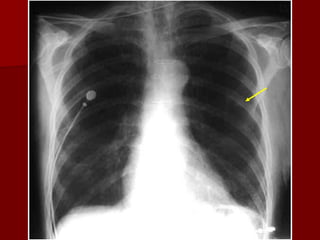

Penetration:

Refers to adequate photons traversing the patient to expose the

radiograph.

 The lack of penetration renders the area “whiter” than with an

adequate film and can simulate pneumonia or effusion.

 In an ideal radiograph the thoracic spine should be barely

perceptual viewing through the cardiac shadow , the left hemidiaphragm behind heart and vessels only up to 2/3 of lung area

In lateral view 2 sets of ribs should be seen, sternum seen,

spine appears clearer as it goes down.

Penetration

SEE THE NODULE ON THE

PREVIOUS FILM

Rotation